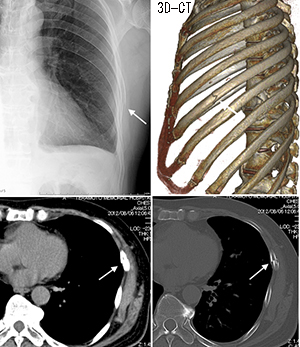

16层螺旋ct多种重建方法在诊断肋软骨骨折中的应用 罕见病 疑难病 会诊平台 专家会诊 网上会诊 医学影像

16层螺旋ct多种重建方法在诊断肋软骨骨折中的应用 罕见病 疑难病 会诊平台 专家会诊 网上会诊 医学影像

16层螺旋ct多种重建方法在诊断肋软骨骨折中的应用 罕见病 疑难病 会诊平台 专家会诊 网上会诊 医学影像